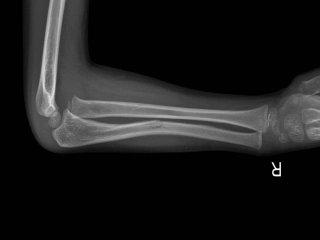

孟泰贾骨折(Monteggiafracture)系尺骨上1/3骨折合并桡骨小头脱位。儿童孟氏骨折有多种分类方法,但Bado分类经受住了时间的考验,是目...